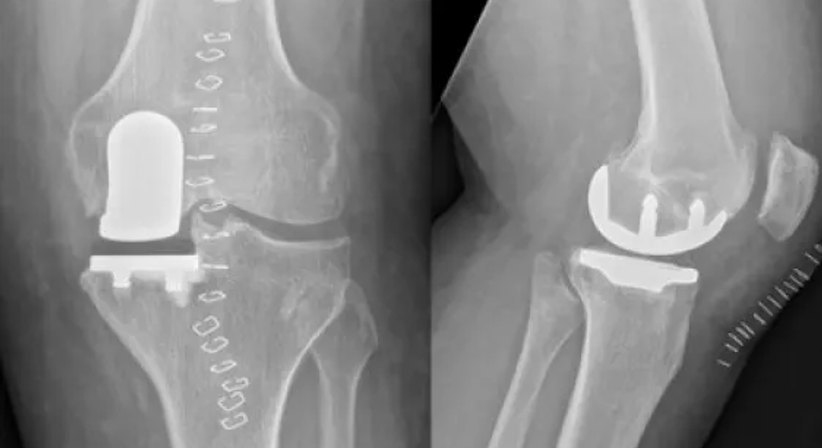

Ein künstliches Kniegelenk wird in der Regel dann notwendig, wenn eine Abnützung des Gelenkknorpels (Arthrose) vorliegt oder das Kniegelenk aufgrund einer Knieverletzung dauerhaft geschädigt ist.

• Totalendoprothese

Mithilfe einer Knietotalendoprothese (kurz Knie-TEP) kann das abgenützte Kniegelenk durch spezielle Oberflächenimplantate vollständig ersetzt werden. Die heutigen modernen Implantate sind sehr langlebig und weisen eine hohe Stabilität auf. Sie fühlen sich wie das eigene Kniegelenk an und ermöglichen dem Patienten auch bei gestrecktem Bein einen sicheren Stand.

• Halbschlittenprothese

Mit einer Halbschlittenprothese wird nicht das ganze Kniegelenk, sondern nur der abgenützte, verschlissene Anteil (entweder der innere, äußere oder hinter der Kniescheibe gelegene Teil) endoprothetisch ersetzt. Sämtliche gesunde Strukturen des Gelenks werden geschont und bleiben anatomisch unverändert. Der Vorteil beim Einsatz einer Halbschlittenprothese liegt in der verkürzten Operations- und Rehabilitationszeit. Aufgrund der rascheren Genesung kann die volle Mobilität in relativ kurzer Zeit wiedererlangt werden.